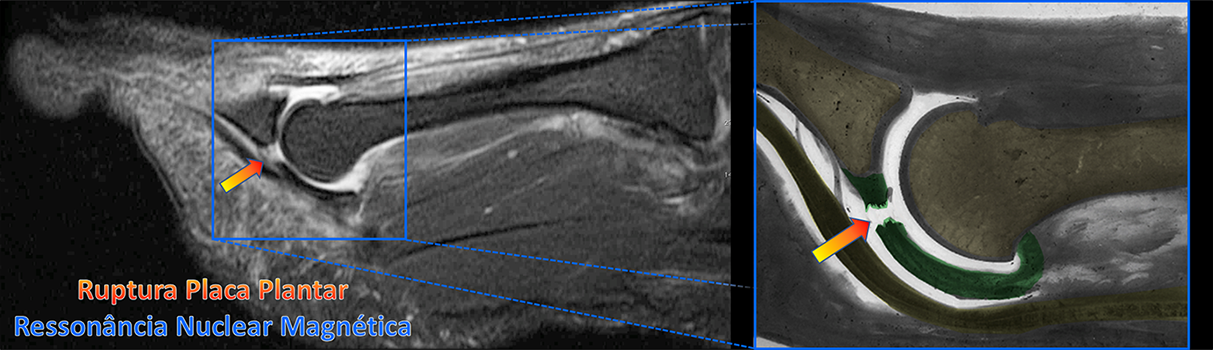

Exames de RX e ressonância nuclear magnética (RNM) podem auxiliar o diagnóstico e avaliar outras alterações ou lesões concomitantes, como fratura de stress, doença de Freiberg e artrose.

Inicialmente a lesão da placa plantar pode ser diminuta e microscópica, apresentando somente um processo inflamatório com dor e edema local. Entretanto, com o aumento progressivo da lesão, a ruptura da placa plantar faz perder a estabilidade articular, o que causa a elevação (deformidade em garra) e o deslocamento lateral do dedo (crossover).